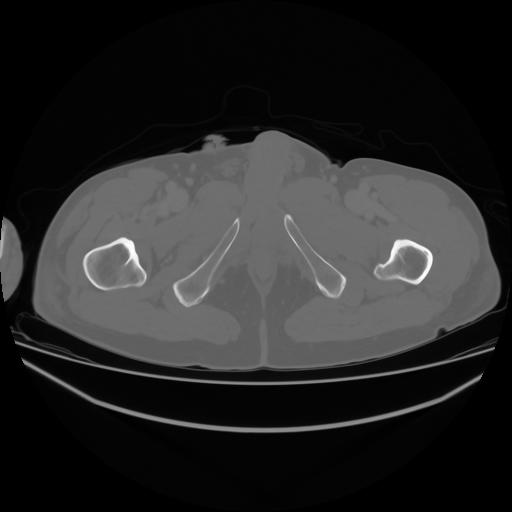

4 CUERPO,CE,Axial,3.0,CUERPO,,